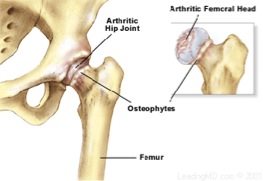

Osteoarthritis (OA) is a condition affecting the cartilage of a joint. The role of cartilage within a joint is to act as a shock absorber to protect the bone and provide a smooth surface for a joint to glide. When OA is present, inflammation affects the cartilage and leads to breakdown of the joint surface and cause pain, swelling and joint deformity.

Diagnosis of OA is based on the individual history and a physical examination of the hip. The groin and lumbar region may also be examined to exclude other conditions and diagnosis can be assisted by getting a plain radiograph of the hip (i.e. X-ray). Many individuals may find OA changes on imaging; however, it is important to determine whether these changes are symptomatic.